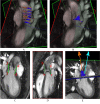

Methods: This paper reports an investigation in 18 pediatric BAV patients and 10 normal controls of links between abnormal blood flow patterns in the ascending aorta and aortic dilatation using velocity-encoded cardiovascular magnetic resonance. Blood flow patterns were quantitatively expressed in the angle between systolic left ventricular outflow and the aortic root channel axis, and also correlated with known biochemical markers of vessel wall disease.

Results: The data confirm larger ascending aortas in BAV patients than in controls, and show more angled LV outflow in BAV (17.54 +/- 0.87 degrees) than controls (10.01 +/- 1.29) (p = 0.01). Significant correlation of systolic LV outflow jet angles with dilatation was found at different levels of the aorta in BAV patients STJ: r = 0.386 (N = 18, p = 0.048), AAO: r = 0.536 (N = 18, p = 0.022), and stronger correlation was found with patients and controls combined into one population: SOV: r = 0.405 (N = 28, p = 0.033), STJ: r = 0.562 (N = 28, p = 0.002), and AAO r = 0.645 (N = 28, p < 0.001). Dilatation and the flow jet angle were also found to correlate with plasma levels of matrix metallo-proteinase 2.